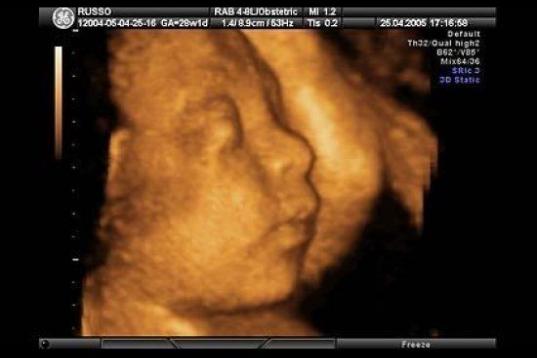

En esta galería puedes ver en fotos como es el desarrollo de un feto de semana en semana:

Desarrollo del feto, en fotos